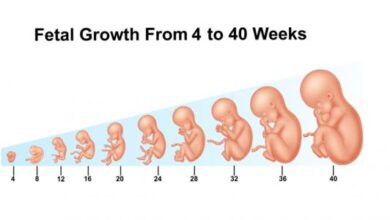

تعتبر فترة الحمل في الشهر الخامس من أكثر الفترات التي ترتاح فيها السيدة الحامل، وذلك بسبب التخلص من أغلب أعراض الحمل المزعجة، ويبدأ توقيت هذا الشهر من الأسبوع الثامن عشر إلى الأسبوع الواحد والعشرين، ويزداد نمو الجنين خلال هذا الشهر بشكلٍ ملحوظ، كما يزداد حجم بطن الأم بالتزامن مع زيادة وزن الجنين وحجمه، وسيتم في هذه المقال عرض التطور في شكل الجنين وحجمه في الشهر الخامس من الحمل.

- الأسبوع الثامن عشر: يصل طول الجنين خلال هذا الأسبوع إلى ما يقارب ال14 سم، ويصل وزنه إلى حوالي 141 غراماً، وتشعر الأم خلال هذه الفترة بحركة الجنين وركلاته داخل الرحم، كما يمكنها الخضوع لفحص الموجات الفوق صوتية وملاحظة جنينها يتثاءب، بالإضافة إلى ذلك، يتطور الجهاز المناعي لدى الجنين في هذا الأسبوع.

- الأسبوع التاسع عشر: يصل طول الجنين خلال هذه الأسبوع إلى حوالي 15 سم، ويصبح وزنه يقارب ال226 غراماً، ويكتمل نمو اليدين والرجلين، كما ترتبط الخلايا العصبية لتصل بين الدماغ والعضلات.

- الأسبوع العشرون: يصل طول الجنين في هذا الأسبوع ليصل حوالي 16.5 سم، ويزداد وزنه بشكل ملحوظ ليصبح يقارب ال 283 غراماً، وعلى الرغم من أن حجمه كبير، إلا أنه ما زال قادراً على التحرك بكل حرية في رحم الأم، ويستطيع الأهل هنا تحديد نوع الجنين من خلال التوجه إلى الطبيب المختص، والخضوع للموجات الفوق صوتية.

- الأسبوع الواحد والعشرون: يصل طول الجنين في هذا الأسبوع ليصبح حوالي 18 سم، ويصبح وزنه يقارب ال311 غرام، وبالرغم من التحرك بشكل مستمر، إلا أنه ما زال يحصل على ما يقارب ال12 إلى 14 ساعة من النوم يومياً.